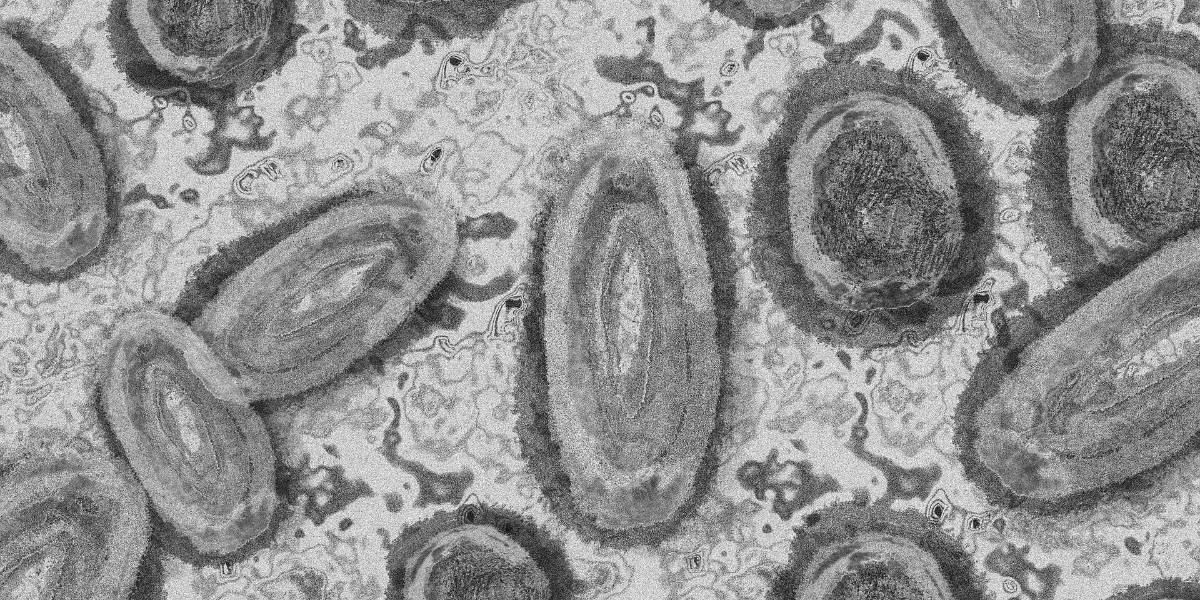

Ecuador está en lista de espera para adquirir vacunas contra la viruela del mono, según anunció el Ministerio de Salud que busca comprar dosis en Suiza y Canadá, sin embargo, esto aún es incierto pues hay poca producción de este fármaco.

El viceministro de Gobernanza y Vigilancia de Salud, Francisco Pérez, aseguró estar golpeando puertas a farmacéuticas de Suiza y Canadá para comprar vacunas que sirvan para frenar la propagación de la viruela del mono.

Cada vacuna contra viruela del mono cuesta 100 dólares en farmacéuticas, mientras los médicos recomiendan el lavado de manos porque advierten que los contagios también se reportan por el contacto de superficies que hayan sido tocadas por los infectados.

El país no está exento de que el número de contagios siga creciendo porque hasta el momento Ecuador registra 6 casos confirmados de viruela del mono, cuatro de ellos fueron detectados en Guayaquil. Frente a esa situación, epidemiólogos piden medidas urgentes para frenar la propagación del virus.